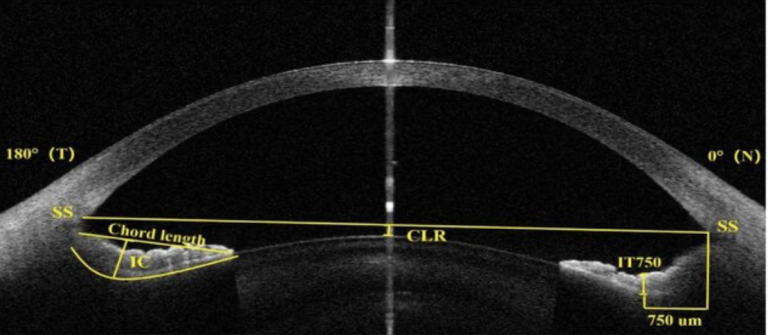

Préservation de la vision par ANX007 : résultats cliniques et changements anatomiques de l’essai Archer de phase 2 Lire la suite